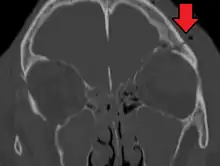

| Basilar skull fracture | |

| A subtle temporal bone fracture as seen on a CT scan | |

A basilar skull fracture typically requires a significant degree of trauma to occur.[1] It is defined as a fracture of one or more of the temporal, occipital, sphenoid, frontal or ethmoid bone.[1] Basilar skull fractures are divided into anterior fossa, middle fossa and posterior fossa fractures.[1] Facial fractures often also occur.[1] Diagnosis is typically by CT scan.[1]